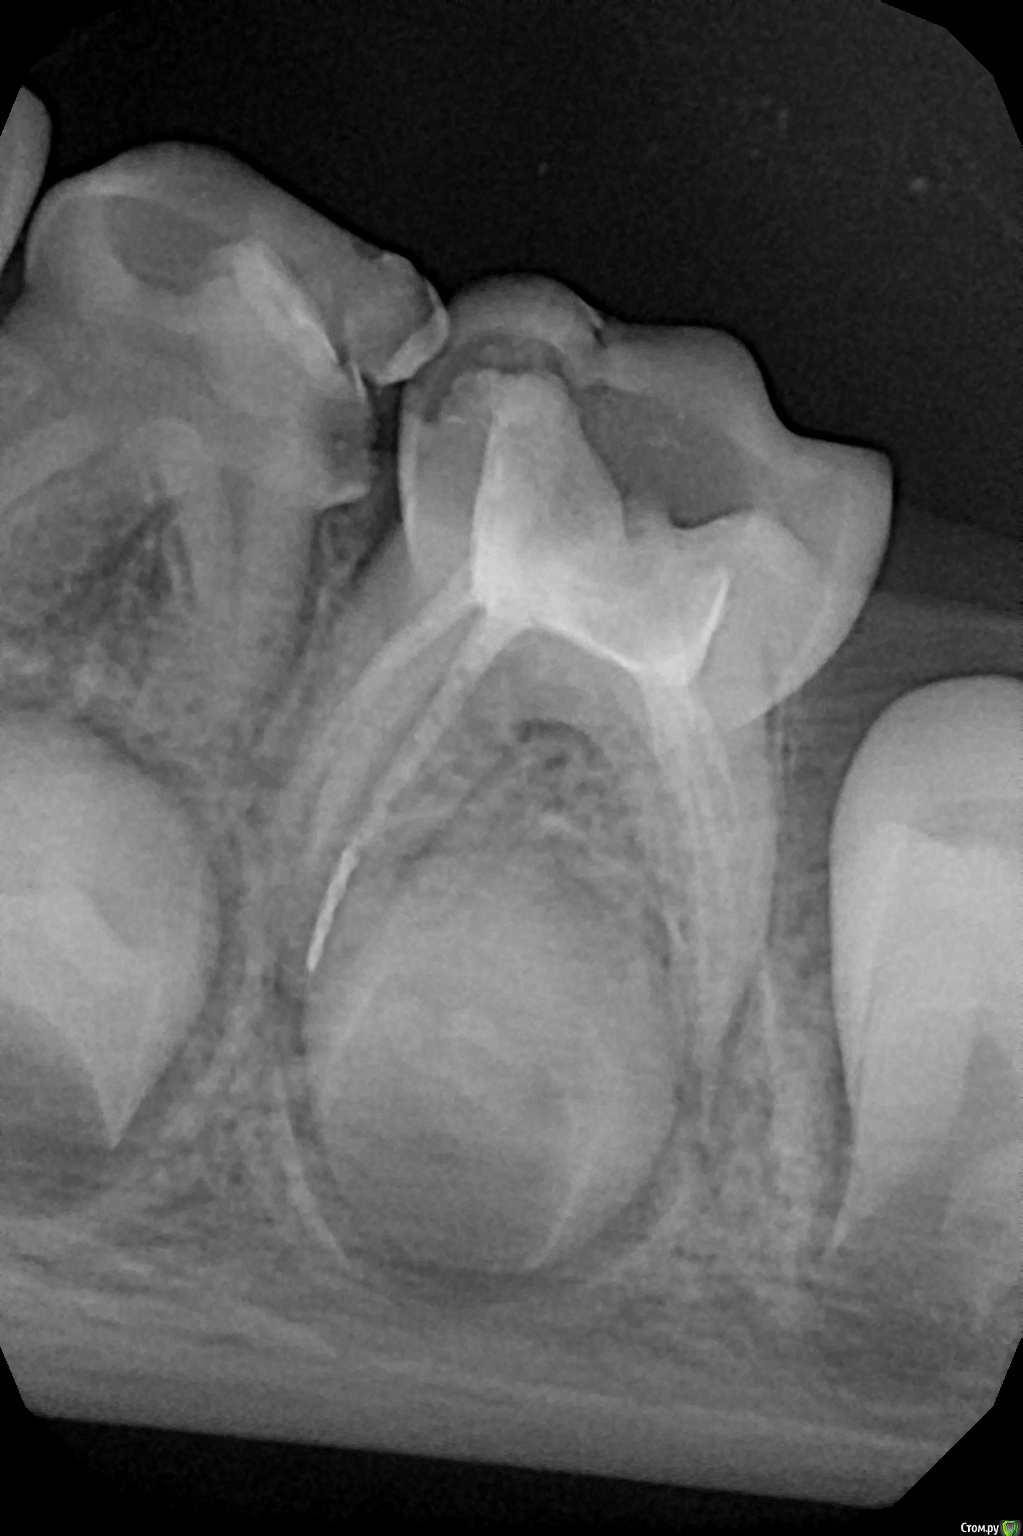

crown Опубликовано 31 мая, 2017 Поделиться Опубликовано 31 мая, 2017 Профайл решил остаться в апексе, вылезет потом? Ссылка на комментарий

Давлетшин Опубликовано 1 июня, 2017 Поделиться Опубликовано 1 июня, 2017 Очень интересный клинический случай, понаблюдать бы в динамике. Вариант 1. деструкция костной ткани вокруг корня (инструмент в канале) - на удаление зуб, 2 резорбция корня медиального (инструмент в кости) - на удаление зуб, искать инструмент. 3 плохой вариант. резорбция + деструкция, и инструмент окажется ниже уровня коронки постоянного.- КТ, оценивать, доставать инструмент. Сомневаюсь что инструмент выйдет через свищ. просто упрётся в мягкие ткани. причем есть риск что под действием мышц, или движений слизистой инструмент протолкнётся куда нибудь глубже. личное мнение, не настаиваю. удалить этот зуб, пациента к ортодонту, врачу спать спокойно. Ссылка на комментарий

Джима Опубликовано 1 июня, 2017 Поделиться Опубликовано 1 июня, 2017 Костик, ты тролль))Не равняй кусок файла с имплантом - не тот возраст и не те условия. У них почти все лишнее из организма вылазит так или иначе. Там же не просто кость, а комплекс тканей, заточенных на смену прикуса. Я тут, по задумке этого же доктора, как-то молочный Пт с дыркой по фуркации триоксидентом лечила ( в каналы кальсепт, сверху триокси) и в дыру малость вывалила - всё лишнее вышло через десну, остальное застыло и зажило, хотя мта вроде как тоже годами в кости лежит и не чирикает. Так что, думаю, что если этот корень будет резорбироваться (что не факт), то копьё через время выйдет. А если не будет резорбироваться, то удалится вместе с зубом ближе к смене.Доктор, а что в каналах? Ссылка на комментарий

crown Опубликовано 1 июня, 2017 Автор Поделиться Опубликовано 1 июня, 2017 (изменено) Доктор, а что в каналах? Как всегда цемент эвгеноловый. Изменено 1 июня, 2017 пользователем crown Ссылка на комментарий

Джима Опубликовано 1 июня, 2017 Поделиться Опубликовано 1 июня, 2017 Так я то и написал. За на каким хреном там копаться? Нагноения какие-то... Нагноение от микробов, а не от куска никель-титана.Кость, микробы там есть точно. Когда дойдёт до этого места, тогда микробы своё и отыграют. Это ж молочки, у них каналы не получается обработать на 100% хорошо. Отсилы на 10 Не трожь ты Альберта, он хирург же, они знаешь сколько какашек за нами выгребают - вот и перестраховываются от всего-всего.ЦОЭ, возможно, замедлит резорбцию корня и зуб уйдёт вместе с этим корнем и с этим инструментом по затруднённой физ.смене. Ссылка на комментарий

Джима Опубликовано 1 июня, 2017 Поделиться Опубликовано 1 июня, 2017 Ппц, молочные каналы ковырять никель-титаном?... А сколько лет киндеру?Доктор, их на полном серьёзе обрабатывают никель-титаном. Я, правда, тоже против этой практики, предпочитаю всё же Н-файлами и гейтсами, но в целом многие детские сейчас это делают. В ДенталФэнтези молочные каналы обрабатывают профайлами. Ссылка на комментарий

сирена Опубликовано 1 июня, 2017 Поделиться Опубликовано 1 июня, 2017 Ну,конкретно меня он пугает тем,что если выйдет в полость рта с гноем или при физсмене,то может путешествовать как угодно.Застрять в глотке,миндалинах или жкт.Зачем об этом думать?Поэтому и говорю:если всё будет нормально - удалить незадолго до физсмены и достать мерзавца.С гноем вряд ли выйдет - застрянет в грануляциях скорее всего.Но надо быть бдительным.ПС:буквально 2 дня назад удаляла нижний седьмой и при удалении такое же "копьё" выпало из корня зуба на корень языка.Убрала быстро,но стресс был неслабый.Нервная работа. Ссылка на комментарий